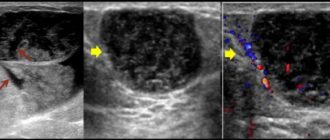

Внутрипротоковая папиллома молочной железы — лечение и удаление По статистике папилломой молочной железы страдает

Папиллома молочной железы лечение консервативное 01 Август 0 просмотров 0 рейтинг Боль в груди